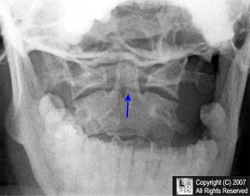

A Mach line is an optical illusion usually appearing as a black line produced by the retina of the observer in response to a border of bone or soft tissue as it interfaces with another, less dense object on a radiograph; Mach lines usually are seen at the base of the dens created by the superimposition of the occiput (blue line below) or the lateral border of the heart at its interface with the air in the lung.